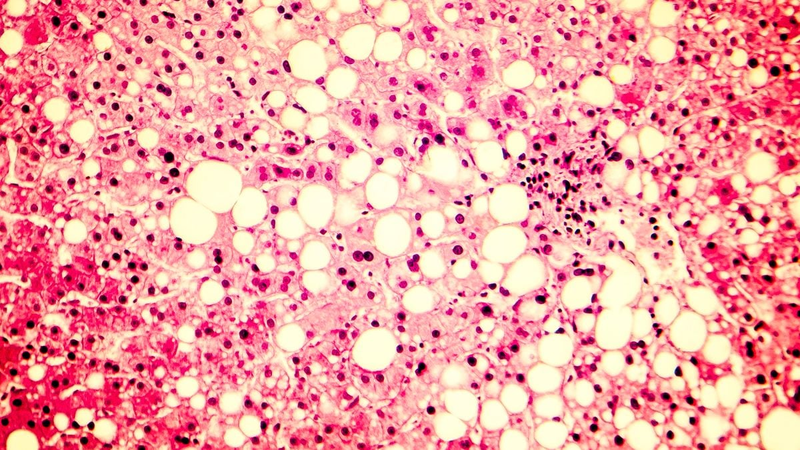

Akero is one of many biotechnology companies that have sought to develop a drug for NASH, a potentially serious condition thought to affect millions of Americans.